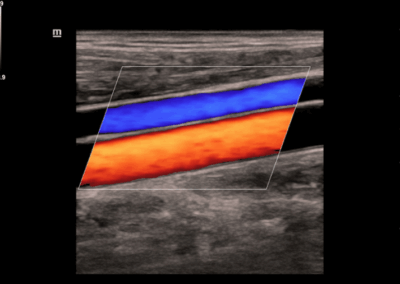

Los sistemas ecográficos estándares disponibles en la actualidad generalmente permiten un diagnóstico básico, pero carecen de funcionalidades avanzadas. Ahora, el DC-30 FullHD es la respuesta perfecta para un rendimiento de imagen de alta calidad, con una pantalla táctil de 21,5 pulgadas y funciones avanzadas como Auto IMT, iScape, elastografía Natural Touch, imágenes con contraste UWN e imágenes Doppler tisulares en el ámbito de las imágenes generales, y Smart OB, Smart face e iLive en el ámbito de la obstetricia.